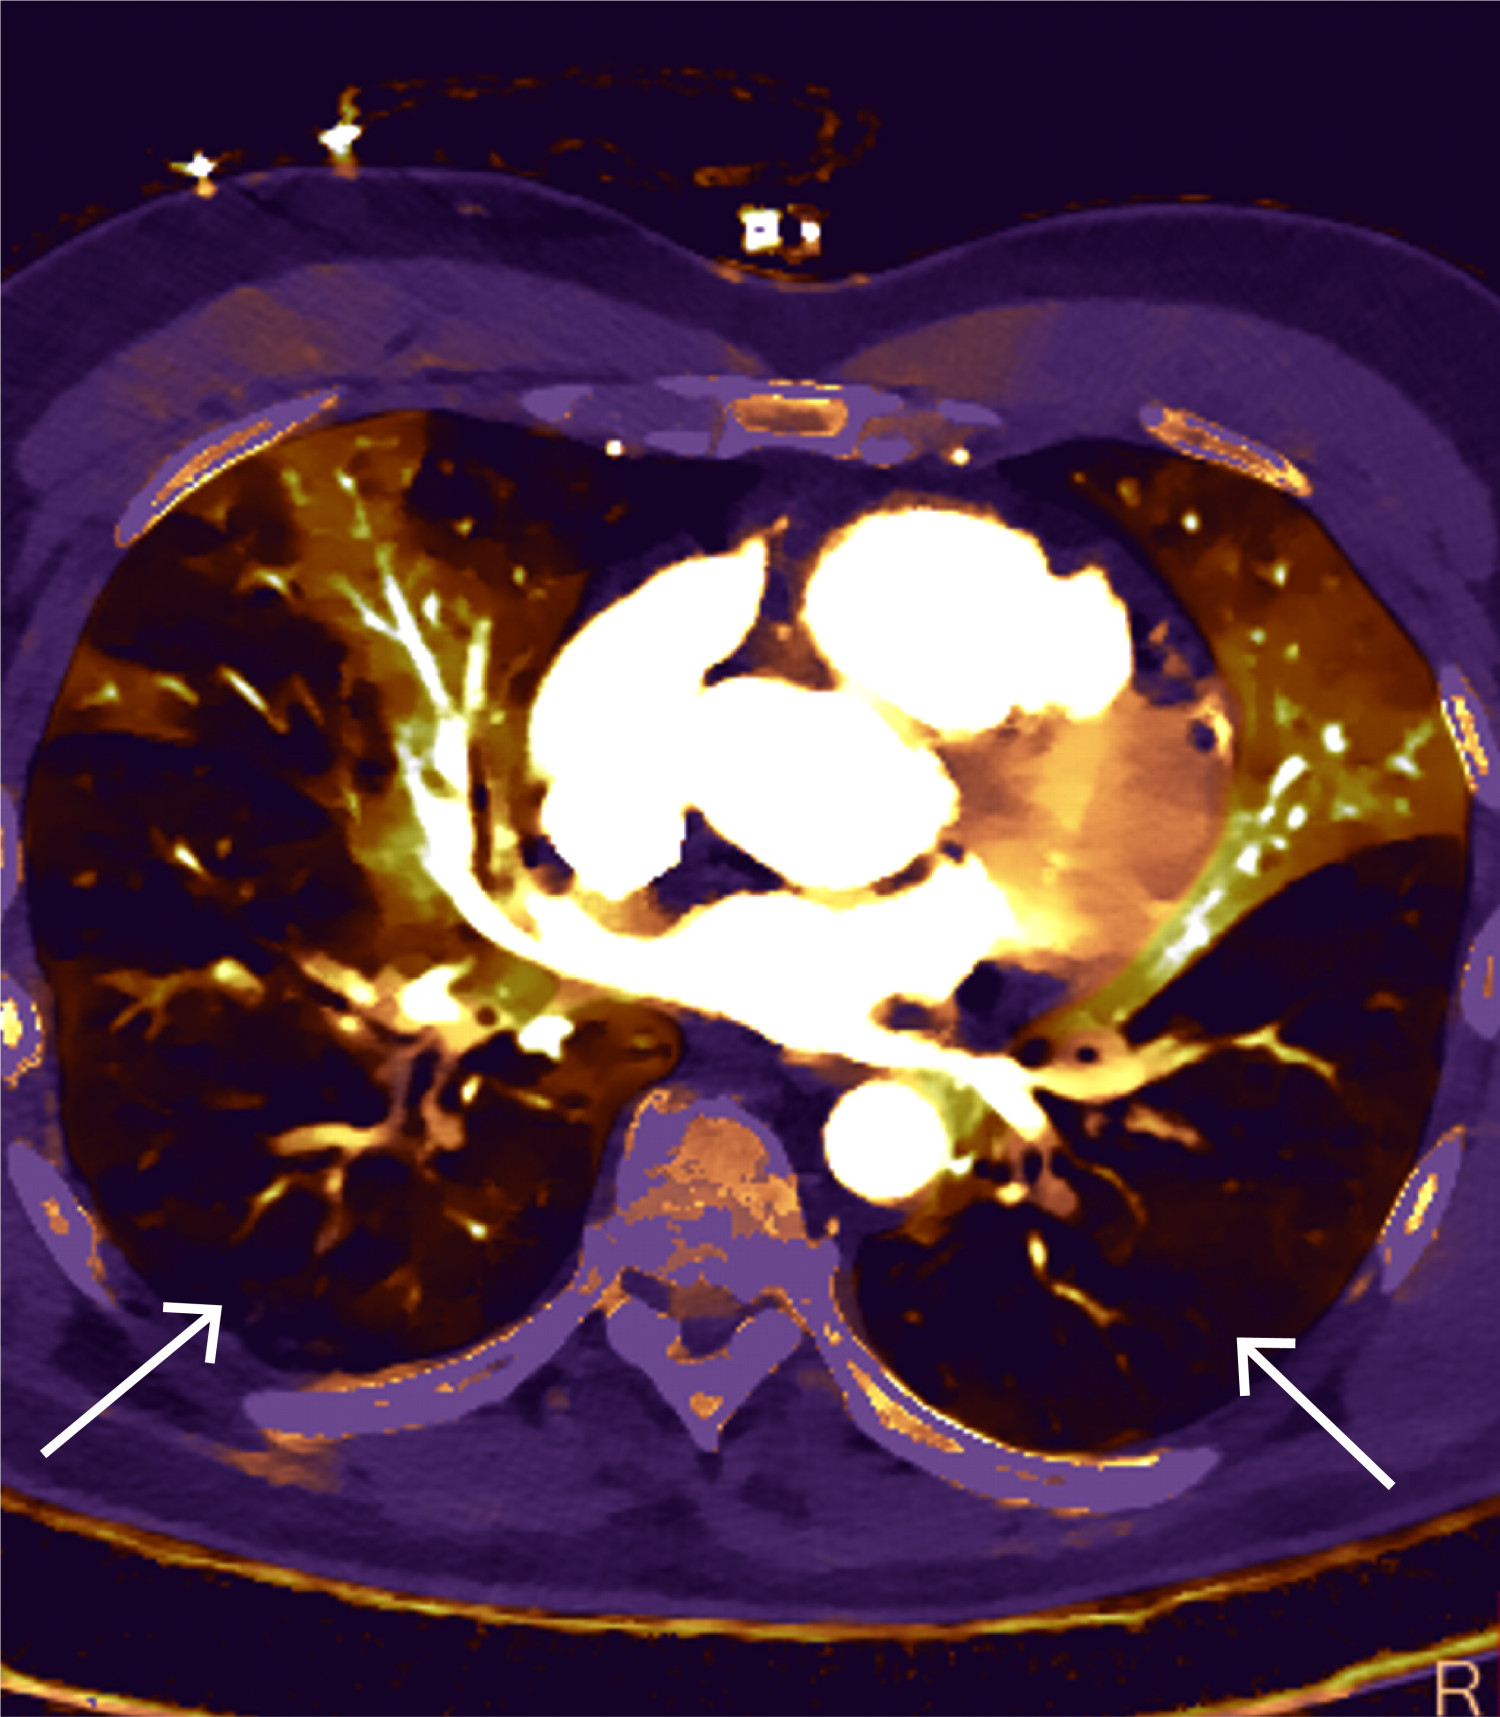

CT toraks med lungeemboliprotokoll viste sadelemboli, med tromber ut i de fleste større lungearterier og med affeksjon av alle lungelapper på lobært og segmentalt nivå (figur 4 og 5). Størst utfall var i underlapper. Aortadisseksjon ble ikke påvist.